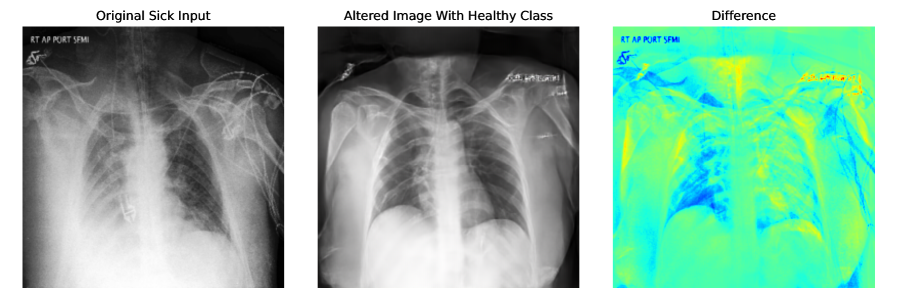

Appendix E More Explainability Results

More explainability results can be found in Figure 6, and Figure 7. Input sick images have been altered to healthy class by adding noise to the input image and denoising with the healthy class. For CheXpert t=0.5 and for ISIC t=0.3 are used. CFG scale is 7.5.

Refer to caption

Figure 6: More explainability results for CheXpert by converting input sick images to healthy images. t=0.5 and CFG=7.5 are used for generating these images.